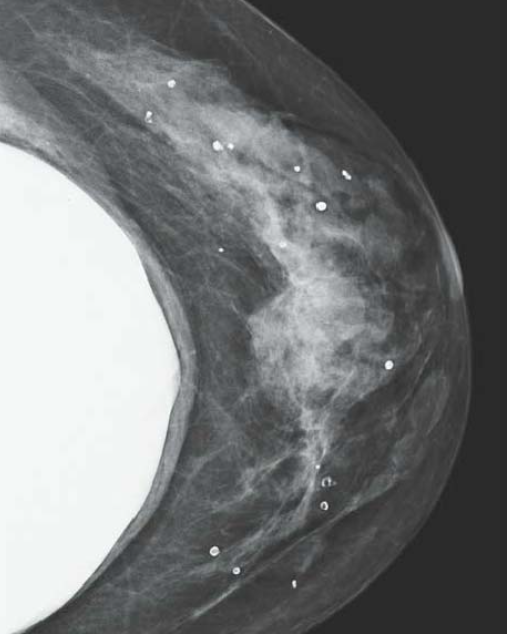

Mammographie

- Ectasie des canaux

- Difficile de distinguer la simple ectasie canalaire de la galactophorite ectasiante (le doppler peut aider)